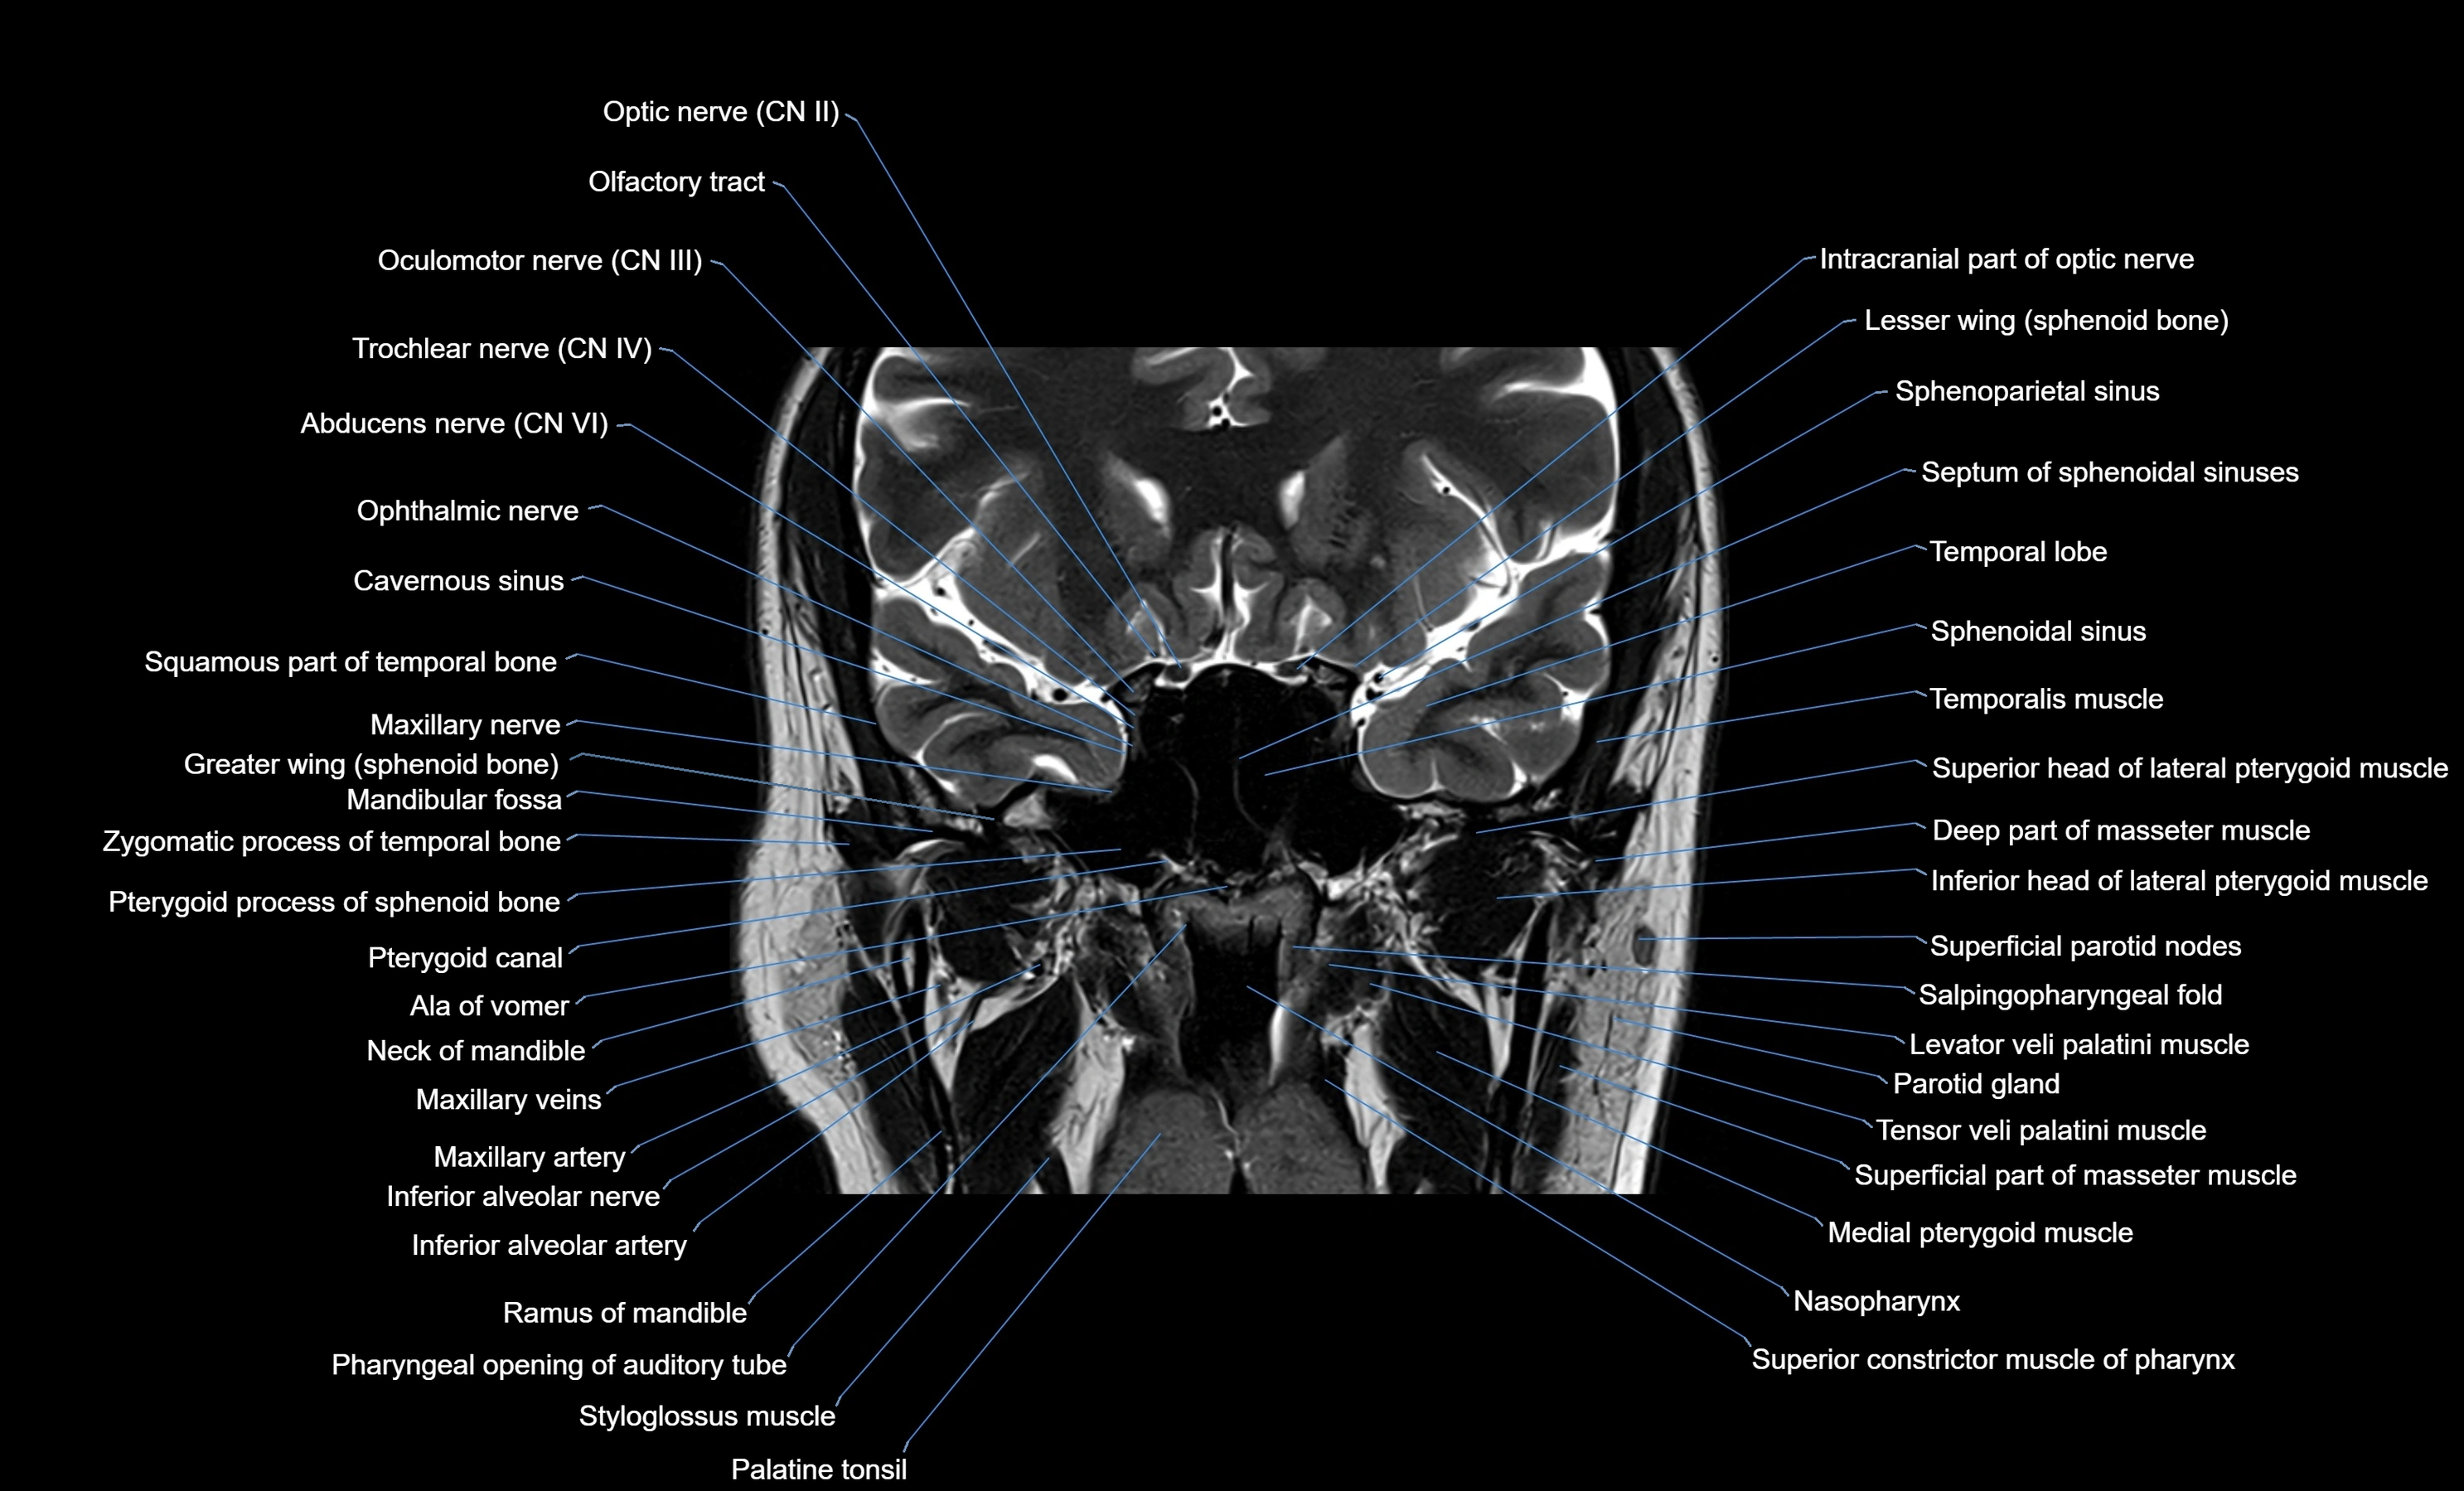

- Abducens nerve (Cranial nerve VI)

- Oculomotor Nerve (Cranial Nerve III)

- Trochlear nerve (Cranial nerve IV)

- Trigeminal nerve (Cranial nerve V)

- Maxillary nerve

- Inferior head of lateral pterygoid muscle

- Superior head of lateral pterygoid muscle

- Medial pterygoid muscle

- Levator veli palatini muscle

- Tensor veli palatini muscle

- Superior constrictor muscle of pharynx